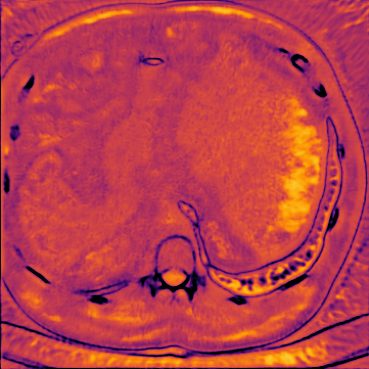

Figure 5 shows an example of a spatio-temporal regularization parameter-map which was estimated using the proposed approach for an acceleration factor of . The network estimates the regularization parameter-map to be pointwise relatively consistenly higher than the spatially required regularization. This result is in fact expected as the temporal dimension is the one for which the gradients of the images are the sparsest because of the high temporal correlation. Further, we see how the network consistently predicts both the spatial regularization as well as the temporal regularization to be less strong in the area where most of the movement is expected, i.e. in the cardiac region.

We compare the 2D time frames of the video samples from the test dataset to the denoised frames, regularized by , and by the spatio-temporal parameter-map . The metrics were calculated frame-wise for all samples at three different noise levels, characterized by the standard deviation of the Gaussian distribution. From the box-plots in Figure 10 we see that the PDHG reconstructions using the proposed spatio-temporal regularization parameter-map yield superior reconstructions compared to and with respect to all measures.Table 3 quantitatively summarizes the results . In Figure 9, we compare two samples from the test dataset with a static camera view in the first row and a dynamic camera view in the third row. The vertical red lines in Figure 9 indicate the -location of the -excerpt shown to the left of each image. The second and the fourth row show the pointwise absolute errors of the respective images. For both samples, the lowest error is achieved by the parameter-map. The spatial and the temporal components of the obtained regularization parameter-maps are visualized in Figure 11. Here, the noisy samples, the results obtained with PDGH using , the spatially and temporally dependent parameter-maps and the ground truth-images are depicted. By comparing the static and dynamic case, we see that the trained CNN is able to differentiate between the two inherently different cases. Thereby, for the video sample with the static camera position, where the background remains constant over time and only objects are changing position, the CNN imposes an overall higher temporal regularization. For the video sample where the camera position also changes over time, the CNN is able to predict the less prominent potential to exploit the temporal gradient-sparsity and thus assigns relatively low